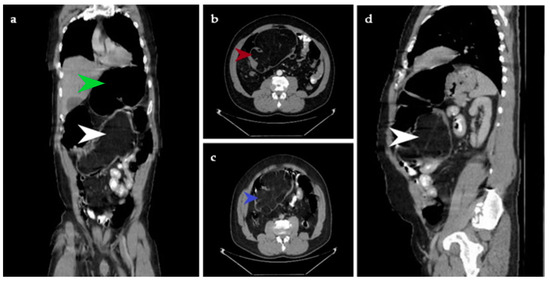

Figure 1. The CT examination with contrast substance reveals, in the coronal plane, voluminous lipoma with measurements of 16/11/12 cm projected in the lumen of the ascending and transverse colon without being able to establish the parietal affiliation. The tumor is indicated with a white arrow. The green arrow shows colonic dilation (a). A transverse section in arterial time reveals a voluminous lipoma, indicated with the red arrow (b). A cross section in venous time shows a lipomatous tumor, indicated with the blue arrow (c). In the sagittal plane, the same tumor is indicated with a white arrow (d). We present the case of a 46-year-old patient who arrives to the Brașov Emergency Department for rectal bleeding with fresh blood and blood clots which started about 12 h prior. The arterial blood pressure value was 100/50 mmHg, the heart rate was 100 bpm, and oxygen saturation (SpO2) = 96%. The patient had no medical family history. He was known to suffer from stage 2 hypertension, and he was a smoker and occasional alcohol user. All these symptoms appeared against a background of abdominal pain that debuted about 2 years ago, accompanied by intestinal transit disorders: constipation followed by diarrhea that relieves the pain. It was initially decided to hospitalize the patient at the Gastroenterology Clinic for investigations and specialized treatment. General clinical examination revealed pale and sweaty facies, and pale skin and mucous membranes. On examination, the abdomen was distended, mobile with respiratory movements, painful in the right iliac fossa, right flank and epigastrium and with no signs of peritoneal irritation. Rectal examination highlighted a normal-looking perianal region, normotonic anal sphincter, normal-sized prostate with preserved median groove and rectal ampulla that contained fresh blood and blood clots. The paraclinical examination detected Hemoglobin (Hb) 7.7 g/dL, Hematocrit (Ht) 21.6%, Serum iron test 34 ug/dL (normally 37–158 ug/dL). Colonoscopy was performed, and blood traces were detected in the colon and at 100 cm from the anal verge there was a large vegetative formation that occupied the entire lumen and could not be passed with the endoscope.